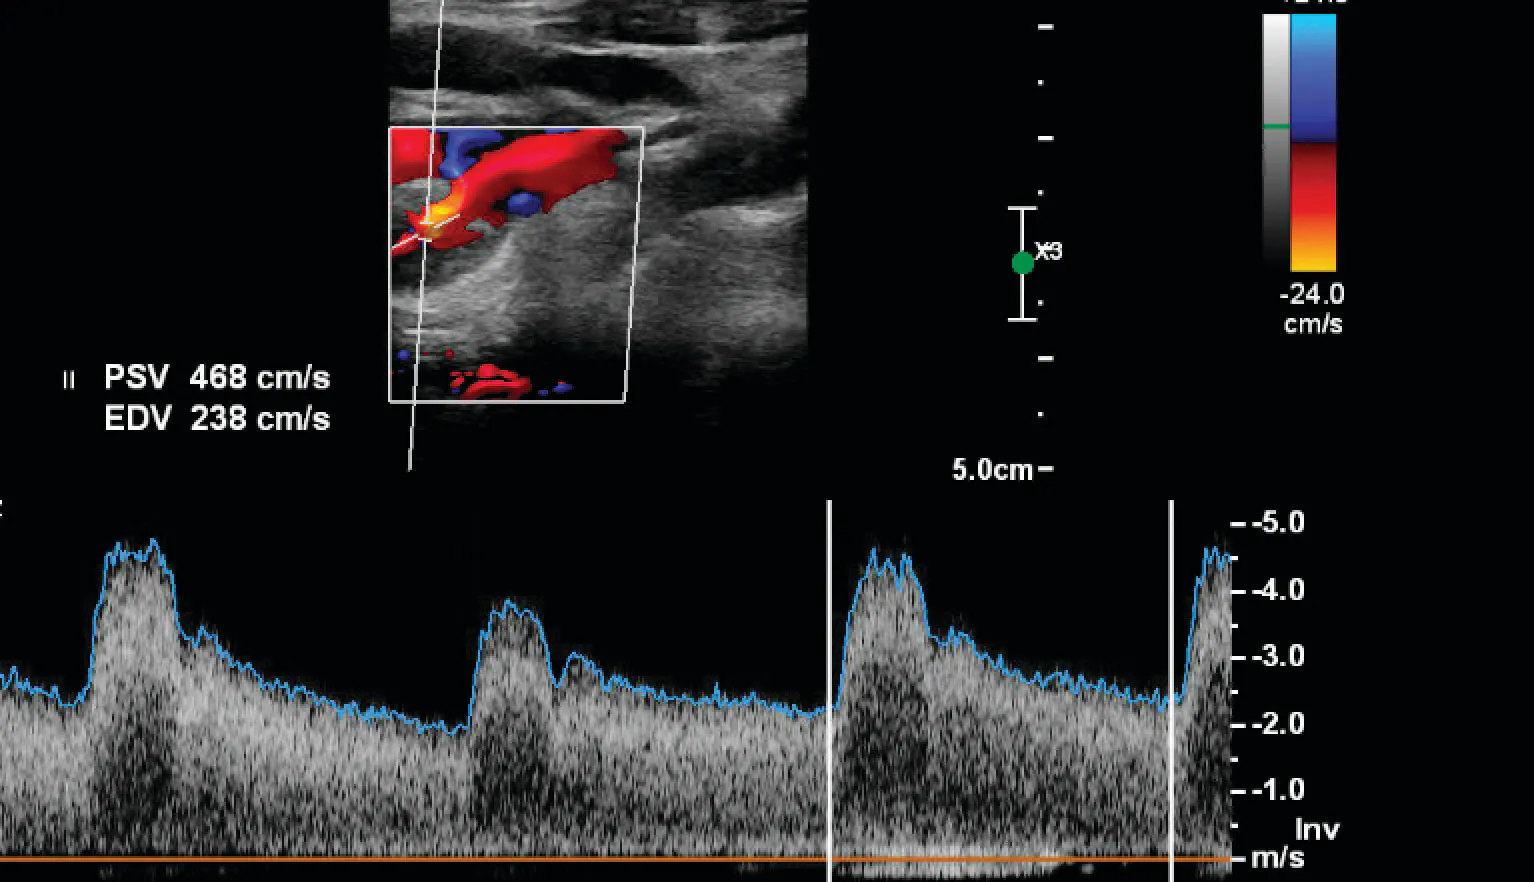

A man in his late 50s with uncontrolled type 2 diabetes, hypertension, dyslipidemia, and morbid obesity was admitted with acute heart failure and a non–ST-segment elevation myocardial infarction. His cardiac catheterization showed severe multivessel disease, and an echocardiogram showed severe left ventricular systolic dysfunction. He was being considered for coronary artery bypass grafting (CABG). His preoperative workup showed a severe to critical right ICA stenosis.

Carotid duplex ultrasound showed > 70% stenosis with a peak systolic velocity (PSV) of 438 cm/s and end-diastolic velocity (EDV) of 238 cm/s, with predominantly hypoechoic plaque (Figure 1) . This was confirmed on a CTA, which showed a type I aortic arch with tortuosity of the innominate artery, a critical proximal right ICA stenosis, and severe tortuosity of the mid to distal ICA.

Figure 1. The carotid duplex images showing > 70% stenosis with a PSV of 438 cm/s and EDV of 238 cm/s with predominantly hypoechoic plaque.